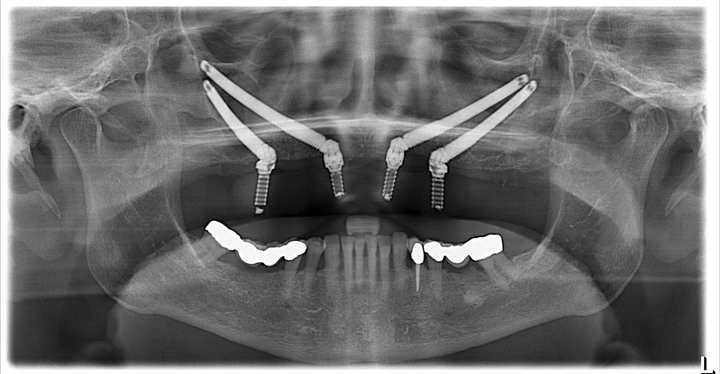

當牙槽骨條件很惡劣時,仲有醫生會將種植體傾斜植入面部,比如話↓: